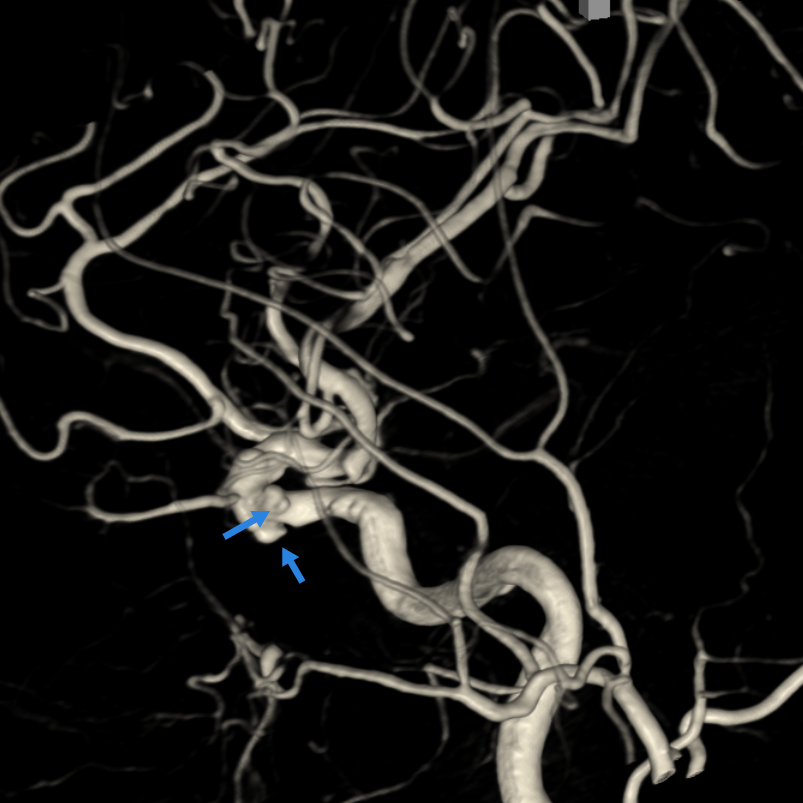

手术当日,在导管室、麻醉科的协作下,神经外科副主任医师刘磊带领介入团队在全麻下为患者实施脑动脉造影+右侧后交通动脉瘤弹簧圈栓塞术。造影显示患者为双侧颈内动脉多发动脉瘤,结合出血位置与动脉瘤形态,团队精准判断右侧后交通动脉瘤为破裂责任病灶。该动脉瘤形态不规则,且瘤颈发出胚胎型大脑后动脉,手术需在完全栓塞动脉瘤的同时确保分支血管通畅。团队克服动脉迂曲与硬化等困难,经过两小时精细操作,成功实现动脉瘤近致密栓塞,载瘤动脉及分支血流通畅。

▲左颈内动脉3D-DSA显示两个动脉瘤(蓝箭头)